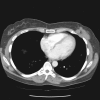

Case presentation: We report a patient with three post-surgical recurrences of fibromatosis of the breast over a seven year period. The fibromatosis was found to be involving the chest wall musculature and causing persistent and worsening pain. An aggressive operative strategy was undertaken, consisting of mastectomy with en bloc resection of the underlying chest wall musculature, ribs, and parietal pleura.